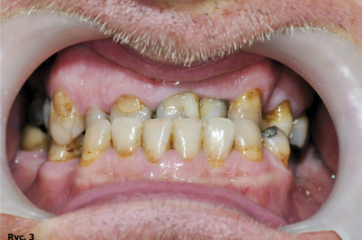

Ponadto w badaniu klinicznym i radiologicznym stwierdzono: konieczność leczenia zachowawczego poszczególnych zębów, obecność braków międzyzębowych w łuku górnym, w łuku dolnym jednostronny brak skrzydłowy i braki międzyzębowe (ryc. 4). Nie stwierdzono zaburzeń w stawie skroniowo żuchwowym. W związku z brakiem pełnych kontaktów zgryzowych wysokość zwarcia była znacznie obniżona.